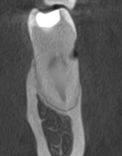

The patient developed gum recession, and the tooth became sensitive to hot and cold. Over time, decay formed on the exposed root surface. The situation was complicated by the fact that the lesion was very close to the nerve — without timely treatment, extraction would have been inevitable.

Our goal was to preserve the natural tooth. First, we carefully removed the decay and restored the damaged area. Then, we performed gum graft surgery using the patient’s own tissue to cover the exposed root and restore its natural protection.